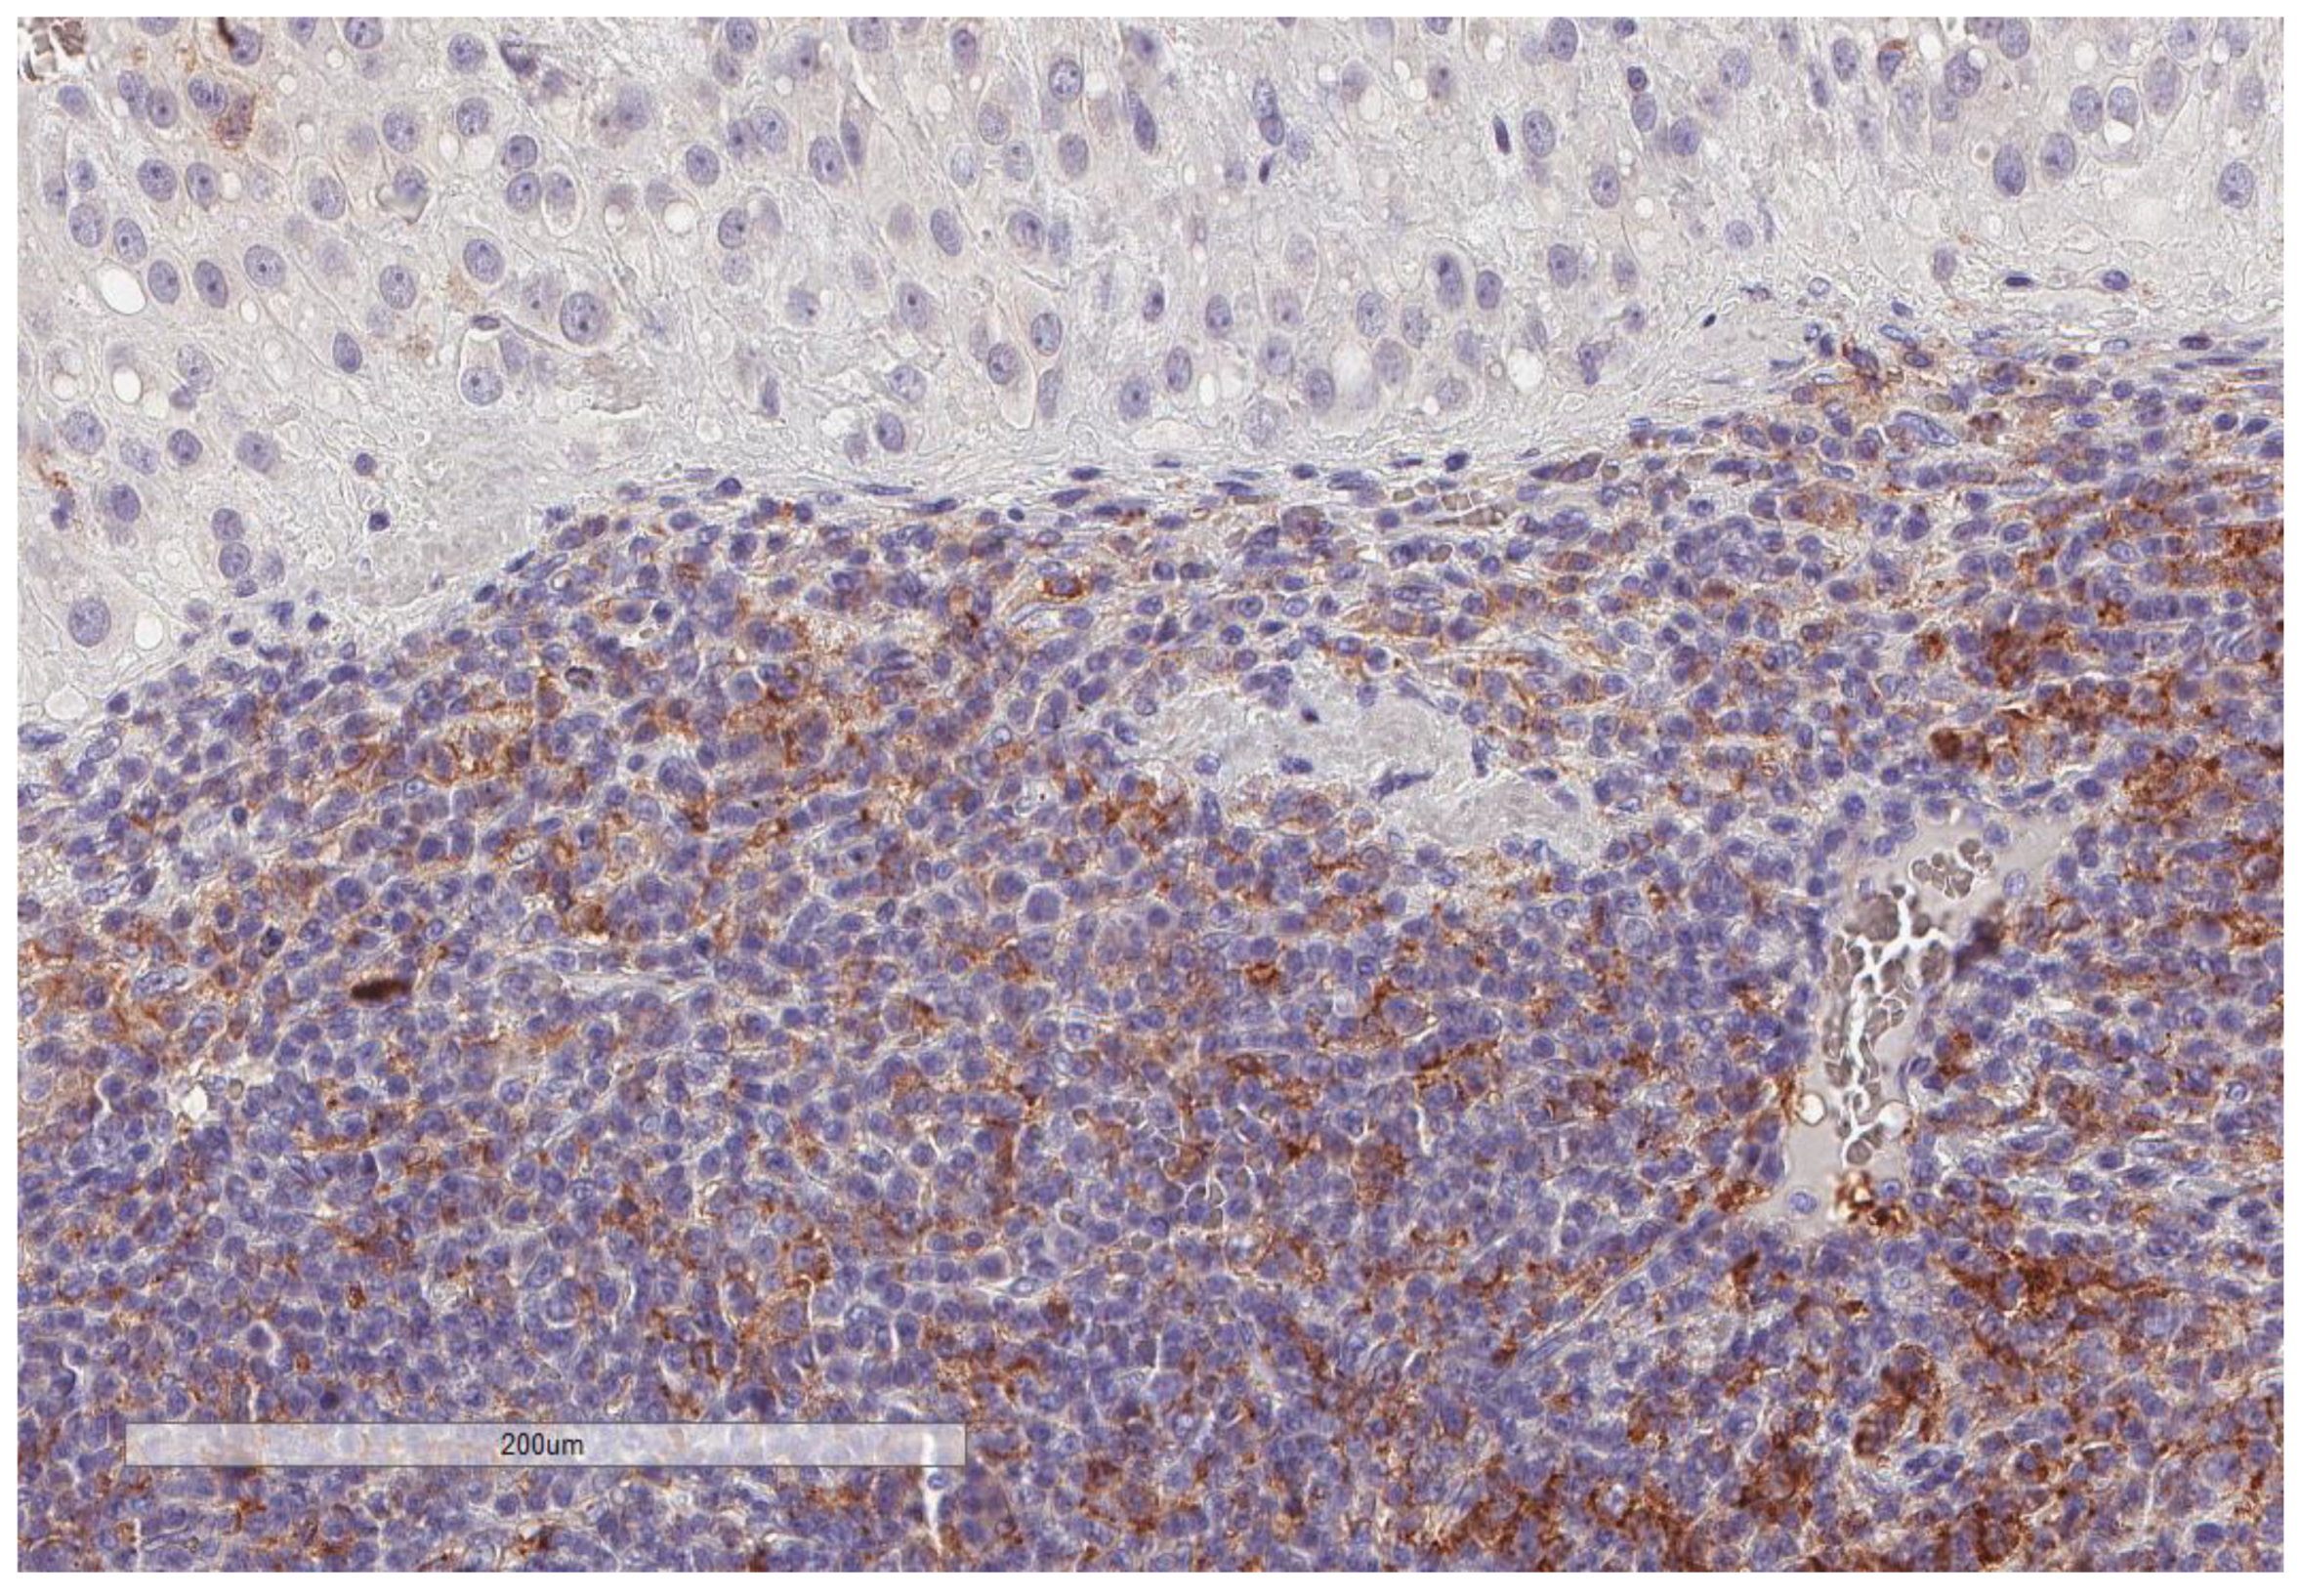

| CD163 (n = 74) | |

| Low (score 0–1) | 45, 60.8% |

| High (score 2–3) | 29, 39.2% |

| PD-L1 inflammatory cells (n = 81) | |

| No (score 0) | 60, 74% |

| Yes (score 1–3) | 21, 26% |

| CD34 vascular density (n = 74) | |

| Range | 1–22 |

| Median (High and Low, n,%) | 3.5 (37, 50% and 37, 50%) |

| Mean ± SD | 5.8 ± 5.7 |

| MECA-79 vessels (n = 59) | |

| High | 5, 8.5% |

| Low | 54, 91.5% |